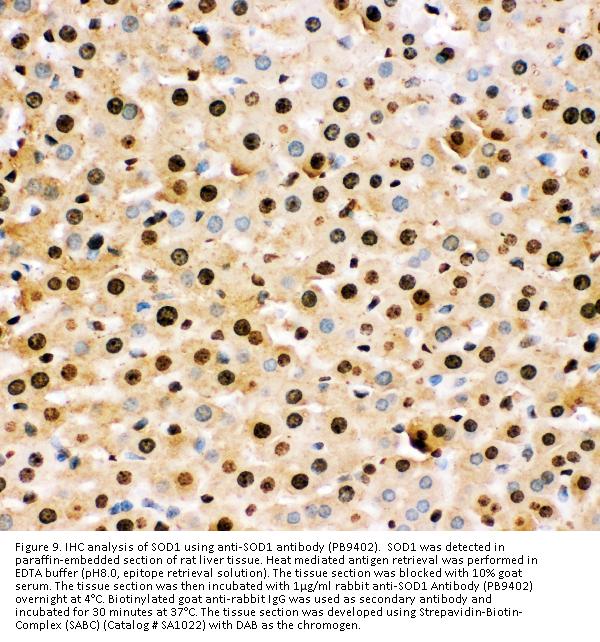

Immunohistochemistry(Paraffin-embedded Section), 2-5 μg/ml, Human

Boster Bio Anti-Superoxide Dismutase 1/SOD1 Antibody Picoband® catalog # PB9402. Tested in Flow Cytometry, IHC, WB applications. This antibody reacts with Human, Mouse, Rat. The brand Picoband indicates this is a premium antibody that guarantees superior quality, high affinity, and strong signals with minimal background in Western blot applications. Only our best-performing antibodies are designated as Picoband, ensuring unmatched performance.